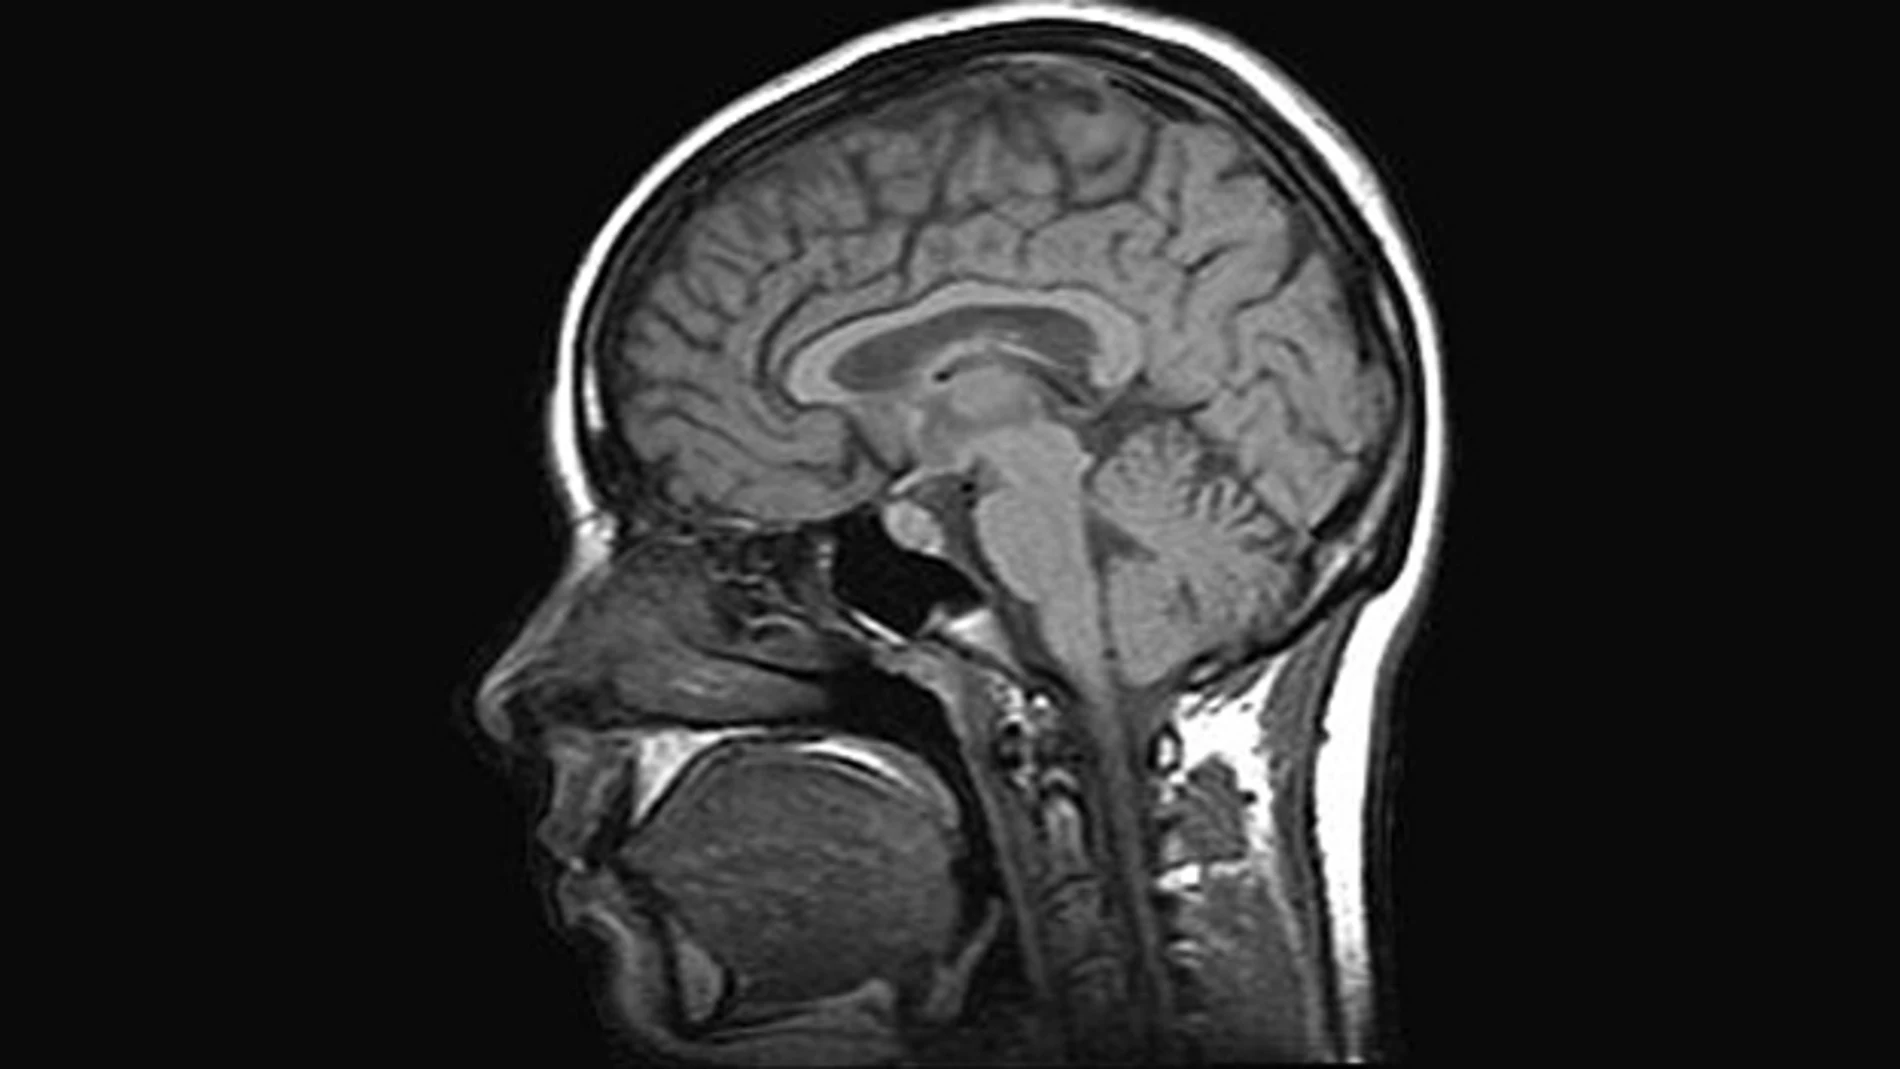

Para ello, la herramienta utiliza rutinas espaciales para analizar las imágenes de resonancia magnética (IRMs), gracias a la experiencia adquirida por Deimos para la ESA al desarrollar rutinas de 'software' que permiten analizar las imágenes por satélite, buscando patrones e identificando elementos específicos.

Los científicos de Deimos utilizan AlzTools para analizar los datos tomados por un escáner cerebral, en vez de un satélite de observación de la Tierra. En lugar de una cosecha o de una carretera, analizan zonas del cerebro como el hipocampo, cuya atrofia está relacionada con el Alzheimer.